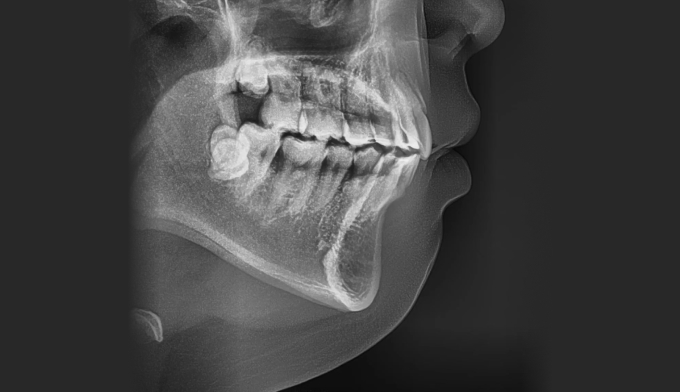

앞니가 돌출되어 있으면서 동시에 위 맨끝 어금니가 아래 어금니와 사선으로 물려있는 가위교합이 관찰됩니다.

총 교정기간은 23개월입니다.